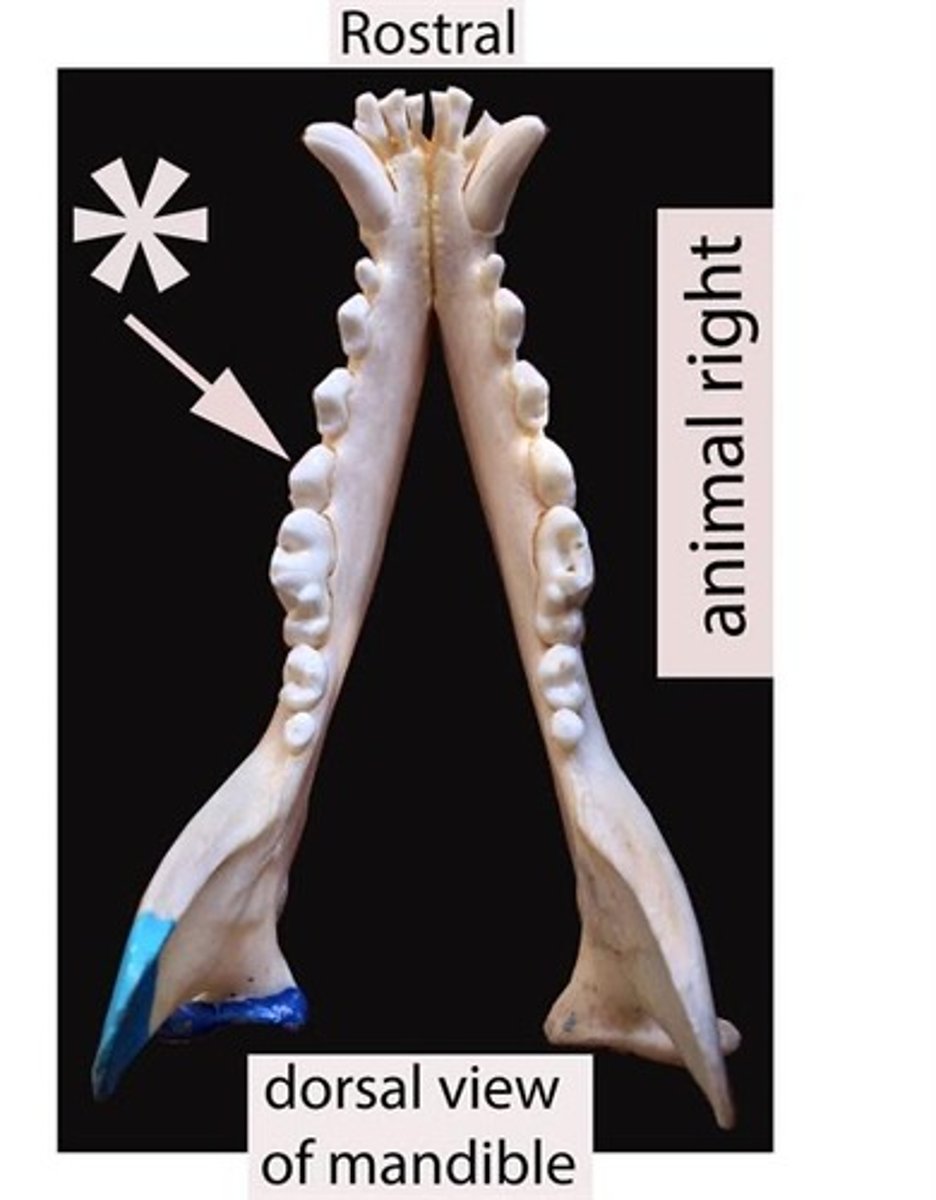

Identify the general type of tooth the arrow is pointing to

Identify the general type of tooth the arrow is pointing to

Identify the general type of tooth the arrow is pointing to

Identify the general type of tooth the arrow is pointing to

Identify the general type of tooth the arrow is pointing to

Identify the general type of tooth the arrow is pointing to

Identify the type of tooth indicated by the arrow.

Identify the type of tooth indicated by the arrow.